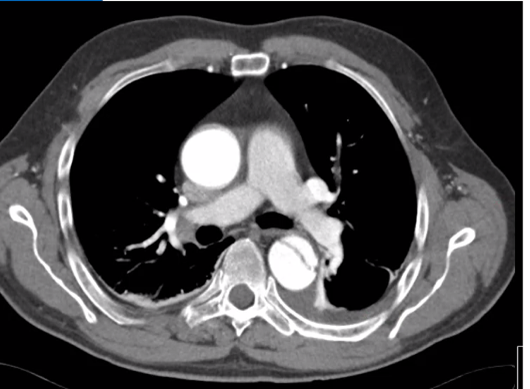

Vad innebär aortadissektion och på vilka sätt kan det ske?

Aortadissektion

Vad ser du på bilden?

Falsk lumen på denna bild